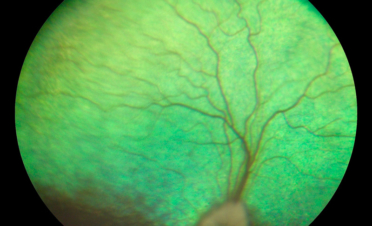

- Retinografía o fotografía de ambas retinas para estudiarlas con mayor detenimiento.

- OCT de retina para ver la estructura del complejo retina-coroides y detectar anomalías como microdesprendimientos, exudados en retina, etc No se observaron anomalías en la retina de ningún ojo, solo un ligero engrosamiento de la coroides en el ojo derecho (el más afectado).